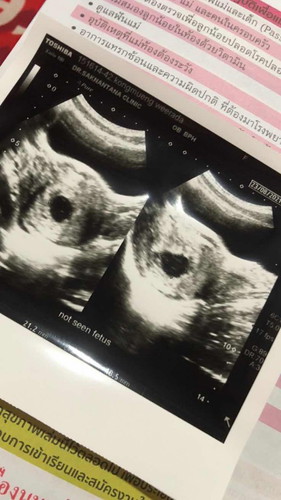

ตั่งครรภ์11สัปดาร์เเล้วค่ะเเต่ตรวจไม่เจอตัวอ่อนมีโอกาศท้องลมไหมค่ะกังวนมาก

มีโอกาสค่ะแต่อย่าพึ่งกังวลนะค่ะแม่เคยเป็นเหมือนกันพึ่งแท้งตอนธันวาคมปี63นี้เองค่ะตอนนี้น้องมาใหม่แล้ว17วีคแล้วค่ะ